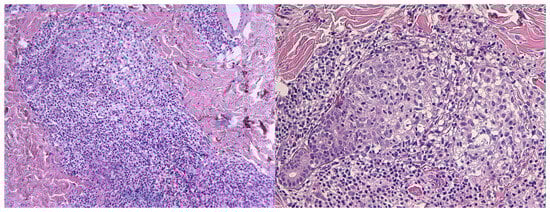

3. Diagnosis

| Folliculotropic mycosis fungoides | Face (esp. head/neck), trunk, extremities | Follicular papules, acneiform lesions, plaques, alopecia, often pruritic, refractory to standard acne therapy | Dense perifollicular infiltrate of atypical CD4+ T-cells with folliculotropism, follicular mucinosis, possible large cell transformation |